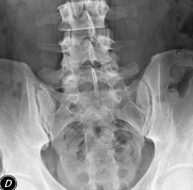

- Pelvis X-ray

This procedure uses X-ray imaging to examine the pelvis, especially the pelvic bones.

- Sacroiliac X-ray

This procedure uses X-rays to examine the sacroiliac joints and rule out inflammatory, traumatic or degenerative diseases.